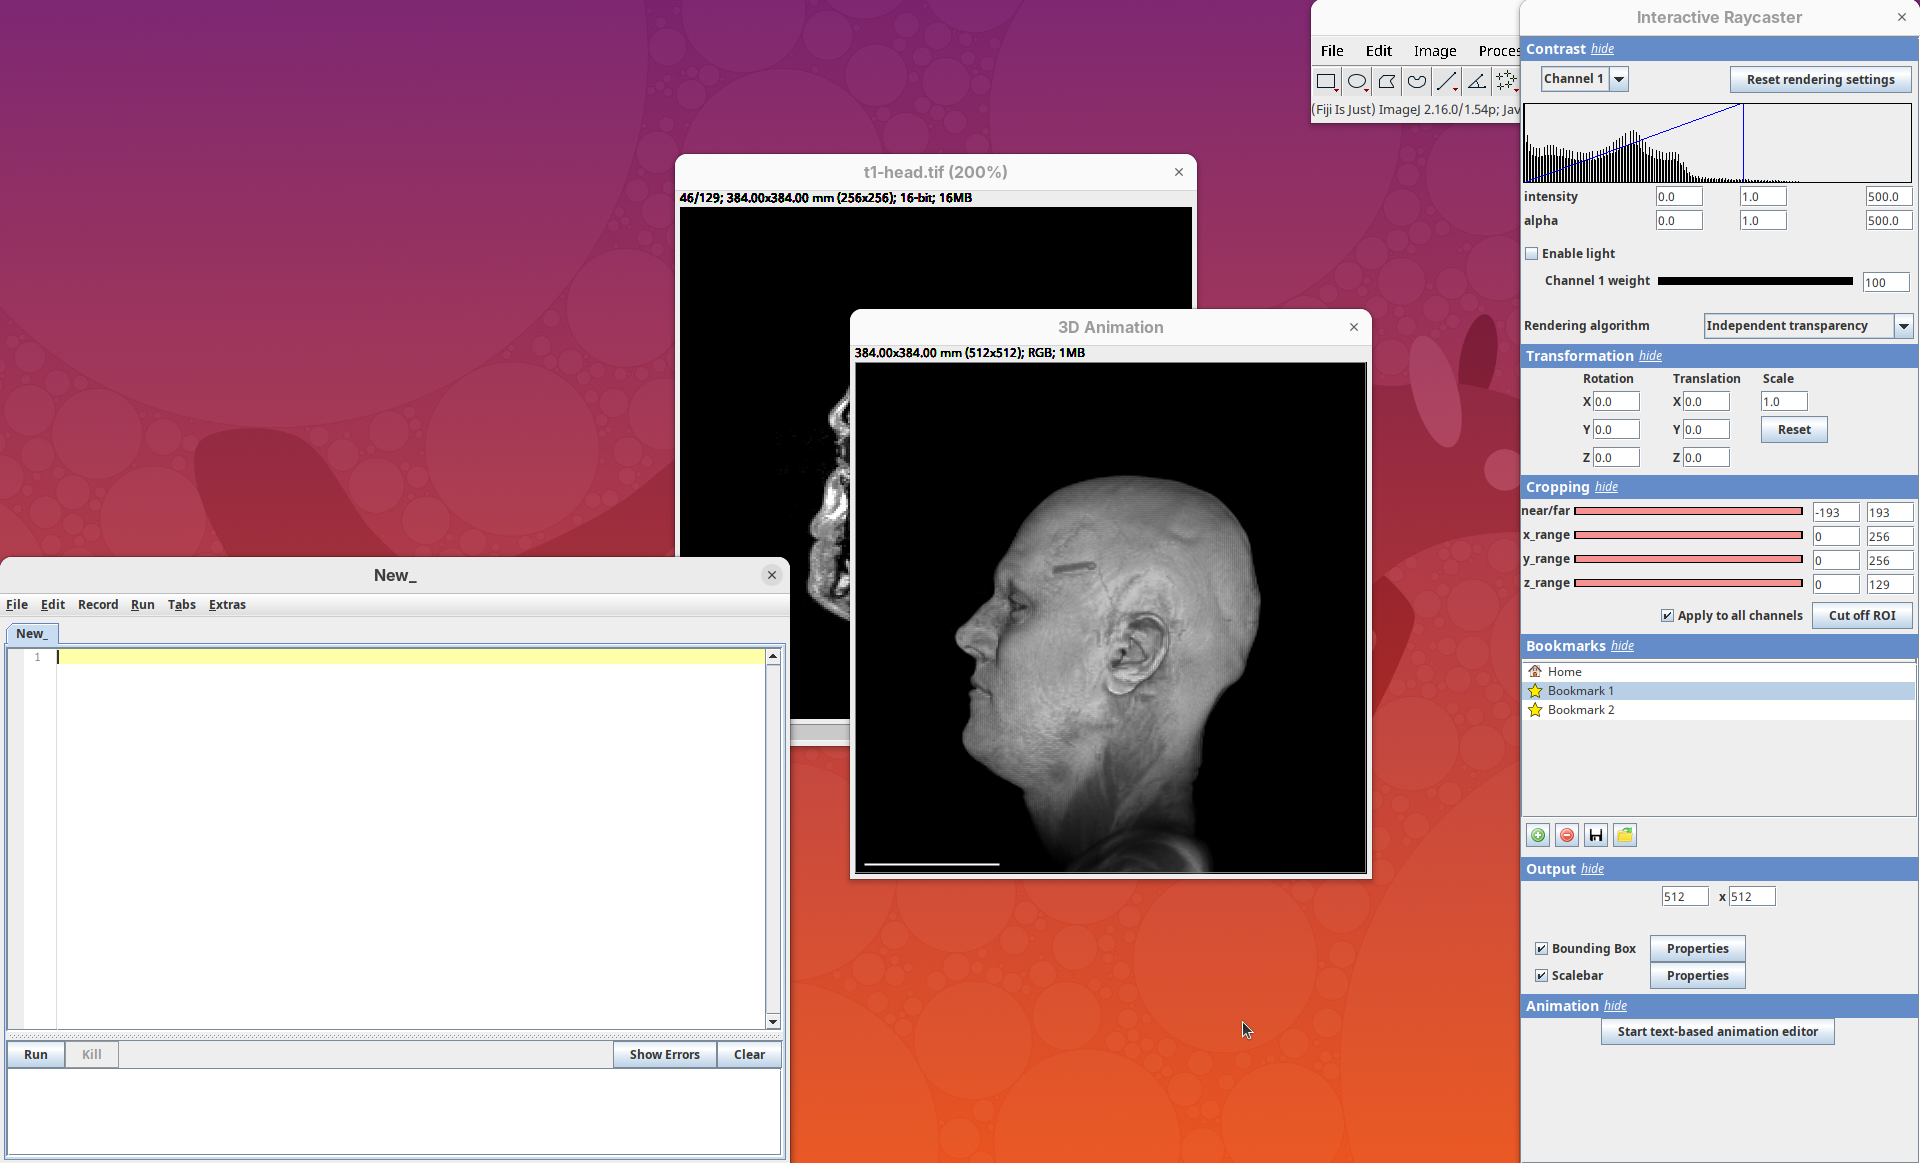

Plugins>3Dscript>Interactive Animation.

Two new windows will open: 3D Animation with the initial rendering of the data and Interactive Raycaster with all the fields to control the rendering parameters.

Contrast

The Contrast section shows a histogram of pixel intensities of the image for each channel, which we can choose using the dropdown menu. We can set the minimum, gamma, and maximum values for the intensity and alpha (transparency) properties of each pixel. The weight option controls the general opacity of the channel (0=invisible, 100=visible). There’s also more advanced options like lighting and rendering algorithm which we’ll simply use the default states as they are usually good for most use cases.

Adjusting the intensity and alpha values is the most impactful way to improve the 3D rendering. With the intensity setting we can define which pixel value in the image corresponds to total black (minimum) and which corresponds to total white. It’s the same as in the standard Brightness & Contrast tool. By default, 3Dscript will load these values from the original stack. In this case, it loaded min=3 and max=521.

Transformation

The transformation menu has controls for rotating, translating, and scaling the sample. We can either add values or manually interact with the 3D Animation window to reorient the sample. Let’s try the latter.

Cropping

Another useful 3Dscript option is the ability to crop the bounding box to show the inside of the sample. We can do it in the XYZ directions or in the near/far axis, defined from the user point of view.

Bookmark

3Dscript allows you to bookmark a view for later inspection. Add the current Contrast, Transformation, and Cropping parameters to the bookmark.

Output

This last panel defines the dimensions of the output animation. By default it uses the original stack dimensions.

You can also define if the bounding box or the scale bar will be visible (enabled by default).

Animation 3D

Now that we learned the basics of setting up the rendering and view parameters, we can start generating animations of the data.

- Click on the

Animationsection and on theStart text-based animation editorbutton.

This will open a special editor window for writing the animation script.